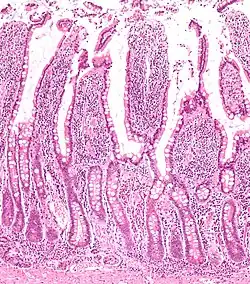

Panethovy buňky se nachází v slizniční membráně tenkého střeva.[1] Jsou umístěny těsně pod střevními kmenovými buňkami v střevních (Lieberkühnových) kryptách.[3] Ojediněle se mohou nacházet v slepém střevě nebo v přívěsku slepého střeva.